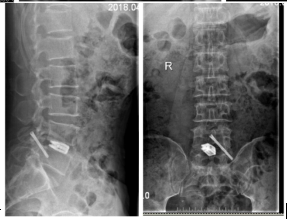

患者:董先生,男,54岁

主诉:腰痛及右下肢疼痛、麻木1月余。查体。

查体:L4、L5棘突间明显压痛、叩痛,腰部活动受限。右侧直腿抬高试验50°阳性,加强试验阳性,

四肢肌力正常,右足背浅感觉减退,余未见明显异常。

诊断:腰椎间盘突出症

手术:经后路L4/5 C臂导航引导下椎间盘摘除、椎间融合、关节突螺钉固定术。

术前

术中

术后